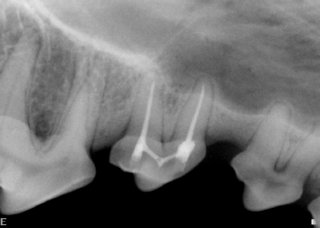

Uncomplicated crown fracture of upper fourth premolar tooth. The pulp chamber is not directly exposed but the dentin is; hence, dentinal tubules are exposed to oral cavity.

Complicated crown fracture of upper fourth premolar tooth. The pulp chamber is directly exposed to oral cavity. The pulp appears black as a result of pulp tissue death due to chronic infection.